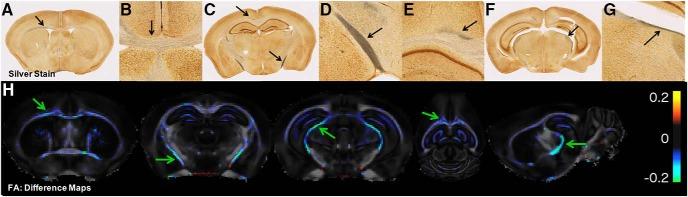

Diffuse axonal injury (DAI) is a hallmark of traumatic brain injury (TBI) pathology. Recently, the Closed Head Injury Model of Engineered Rotational Acceleration (CHIMERA) was developed to generate an experimental model of DAI in a mouse. The characterization of DAI using diffusion tensor magnetic resonance imaging (MRI; diffusion tensor imaging, DTI) may provide a useful set of outcome measures for preclinical and clinical studies. The objective of this study was to identify the complex neurobiological underpinnings of DTI features following DAI using a comprehensive and quantitative evaluation of DTI and histopathology in the CHIMERA mouse model. A consistent neuroanatomical pattern of pathology in specific white matter tracts was identified across DTI maps and photomicrographs of histology. These observations were confirmed by voxelwise and regional analysis of DTI maps, demonstrating reduced fractional anisotropy (FA) in distinct regions such as the optic tract. Similar regions were identified by quantitative histology and exhibited axonal damage as well as robust gliosis. Additional analysis using a machine-learning algorithm was performed to identify regions and metrics important for injury classification in a manner free from potential user bias. This analysis found that diffusion metrics were able to identify injured brains almost with the same degree of accuracy as the histology metrics. Good agreement between regions detected as abnormal by histology and MRI was also found. The findings of this work elucidate the complexity of cellular changes that give rise to imaging abnormalities and provide a comprehensive and quantitative evaluation of the relative importance of DTI and histological measures to detect brain injury.

弥漫性轴索损伤(DAI)是创伤性脑损伤(TBI)病理学的标志。最近,开发了闭合性颅脑损伤旋转加速工程模型(CHIMERA),以在小鼠中产生 DAI 的实验模型。使用扩散张量磁共振成像(MRI;扩散张量成像,DTI)对 DAI 的特征进行描述可能为临床前和临床研究提供一组有用的结果测量。本研究的目的是使用 CHIMERA 小鼠模型中 DTI 和组织病理学的全面和定量评估,确定 DAI 后 DTI 特征的复杂神经生物学基础。在 DTI 图谱和组织学的照片中,在特定的白质束中观察到一致的神经解剖病理学模式。这些观察结果通过 DTI 图谱的体素和区域分析得到了证实,表明在特定区域(如视束)的分数各向异性(FA)降低。通过定量组织学也可以识别出相似的区域,并显示出轴突损伤和强烈的神经胶质增生。使用机器学习算法进行了额外的分析,以确定在没有潜在用户偏见的情况下进行损伤分类的重要区域和指标。该分析发现,扩散指标几乎可以与组织学指标一样准确地识别受伤的大脑。还发现了组织学和 MRI 检测到的异常区域之间的良好一致性。这项工作的结果阐明了导致成像异常的细胞变化的复杂性,并提供了对 DTI 和组织学测量在检测脑损伤方面的相对重要性的全面和定量评估。